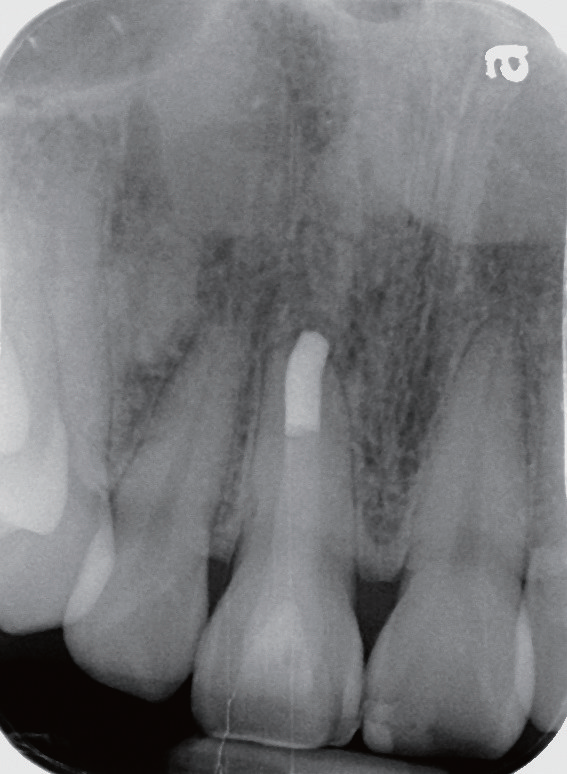

口腔检查   触、扣 诊时,患者表示11较邻牙相比敏感,牙周探诊无异常,肉眼可见11牙冠颜色泽确实和邻牙有所差异(图1),且其唇侧面有数条明显裂纹,而在11的敲扣声音也不像邻牙那般清脆响亮。

图1 11 牙冠颜色相较邻牙暗黄,患者自述按压根部牙龈时略感不适

影像学检查   X线片显示11根尖尚未闭合(或根尖已经吸收),且根管宽大,可见根尖有一约8×10 mm的放射性阴影,周边牙槽骨明显缺损。询问患者自述曾经摔倒过,11受到撞击,不记得具体细节。

诊断与治疗计划   对比11 和12(图2)以及11和21(图3),11 的牙根长度较短,其根尖已出现阴影,按正常发育,11的根管应该不会如此宽大。因而推测患者在7~8 岁时,11应该曾经受到强烈撞击,导致牙髓坏死,使得根管没有继续钙化沉积,造成如今管壁相对较为单薄、根尖仍未完全闭合的情形。因而建议可在不给予局部麻醉下进行11开髓,进一步检查根管内部牙髓组织的实际状态。同时借助显微镜辅助进行根管治疗。